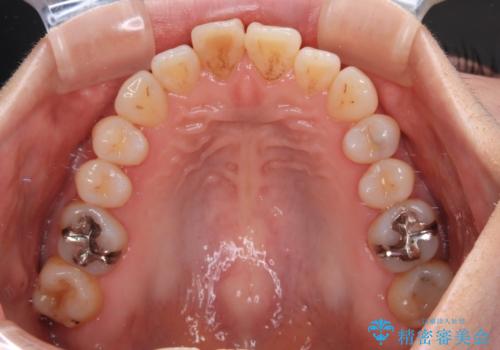

前歯のデコボコをインビザライン・モデレートで矯正治療

- 上下前歯のデコボコを気にして来院された患者様です。

安価なインビザラインパッケージを用いての治療を希望されており、デコボコの程度が中等度であったため、インビザライン・モデレートを用いて矯正治療を行うこととしました。

インビザライン・モデレートは、製作できるアライナーの枚数に制限があるため、移動可能な量に限りがあるものの、インビザライン・ライトよりも枚数が多いため、幅広い症例に対応可能です。